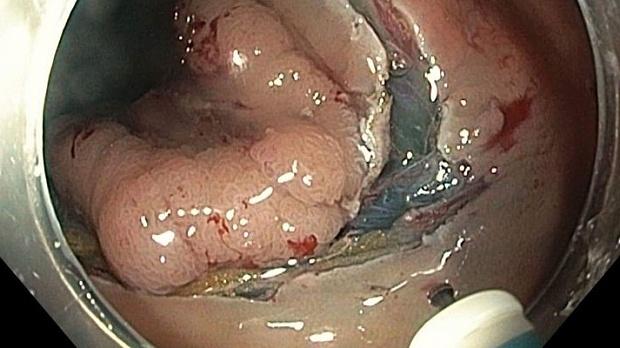

Цель: сравнить медицинские затраты на эндоскопическую подслизистую диссекцию (ЭСД) и трансанальную эндоскопическую микрохирургию. (TEM) для лечения опухолей прямой кишки.

Методы исследования: в анамнезе 80 пациентов, перенесших ЭСД, и 32, перенесших ТЭМ для лечения опухолей прямой кишки. были собраны. Сравниваемые факторы в обеих группах включали возраст пациента, пол и клинические характеристики, а также пребывание в больнице, время процедуры, использование инструментов, лекарства, послеоперационные осложнения, а также визуализация и лаборатория полученные данные. Расходы были проанализированы на основе сборов за медицинское страхование, установленных публично Министерством здравоохранения и социального обеспечения Кореи. Медицинские расходы были также разделены на доплаты пациентам и сборы национальной корпорации медицинского страхования (NHI).

Результаты: характеристики пациентов, включая возраст, пол и сопутствующие заболевания, были схожи в обеих группах, как и процедура. время, гистологический диагноз, размер опухоли и расстояние от анального края, пребывание в больнице и частота осложнений. Медиана общей расходы на госпитализацию в ОУР были значительно ниже, чем в группе Теа (1,214 долл. США против 1,686 долл. США, P < 0.001). Затраты на расходные материалы, лекарства и лабораторные работы, а также плата за эксплуатацию также были значительно ниже, чем в ОУР. в группе ТЭМ. Тем не менее, выплаты пациентам в группе ЭСД были значительно выше, чем в группе ТЭМ (928 долл. против 496 долл., Р < 0,001), поскольку процедура ЭСД при опухолях прямой кишки еще не охвачена корейской НХИ. Заключение: общие прямые медицинские затраты были значительно ниже для ЭСД, чем для ТЭМ при лечении опухолей прямой кишки. [Ann Surg Treat Res 2015;89 (4): 2